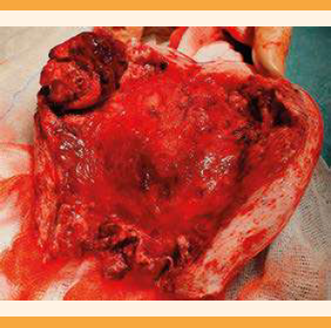

Ante los hallazgos se solicitó la interconsulta con el angiólogo y el cirujano vascular, que desestimó la embolización de las arterias uterinas debido al gran tamaño de la malformación arteriovenosa y el alto riesgo de fracaso del tratamiento, debido a la complejidad del conglomerado vascular uterino. Ante el alto riesgo de hemorragia potencialmente letal y los deseos genésicos cumplidos de la paciente, se procedió a la histerectomía total simple, por vía laparotómica (Figura 2). El análisis histológico informó que la pieza de histerectomía contenía restos placentarios adheridos en la cavidad endometrial (pólipo placentario) y las áreas miometriales, con estructuras vasculares de calibres variables, algunas muscularizadas, compatibles con una malformación arteriovenosa adquirida.

Figura 2 Pieza quirúrgica del útero con sección sagital en la cara anterior donde se objetiva la formación pseudonodular con áreas vasculares de gran calibre.